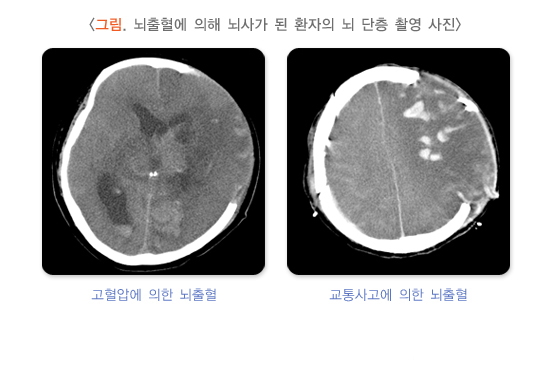

뇌사의 주요 원인은 교통사고, 낙상, 총기 사고와 같은 외상성 뇌출혈, 뇌졸중, 뇌종양 등 뇌질환에 의한 손상입니다. 또한 질식, 익사, 심근경색으로 인해 산소 공급이 차단되면서 발생한 뇌손상도 원인이 될 수 있으며, 전체 사망의 약 1% 정도를 차지합니다.